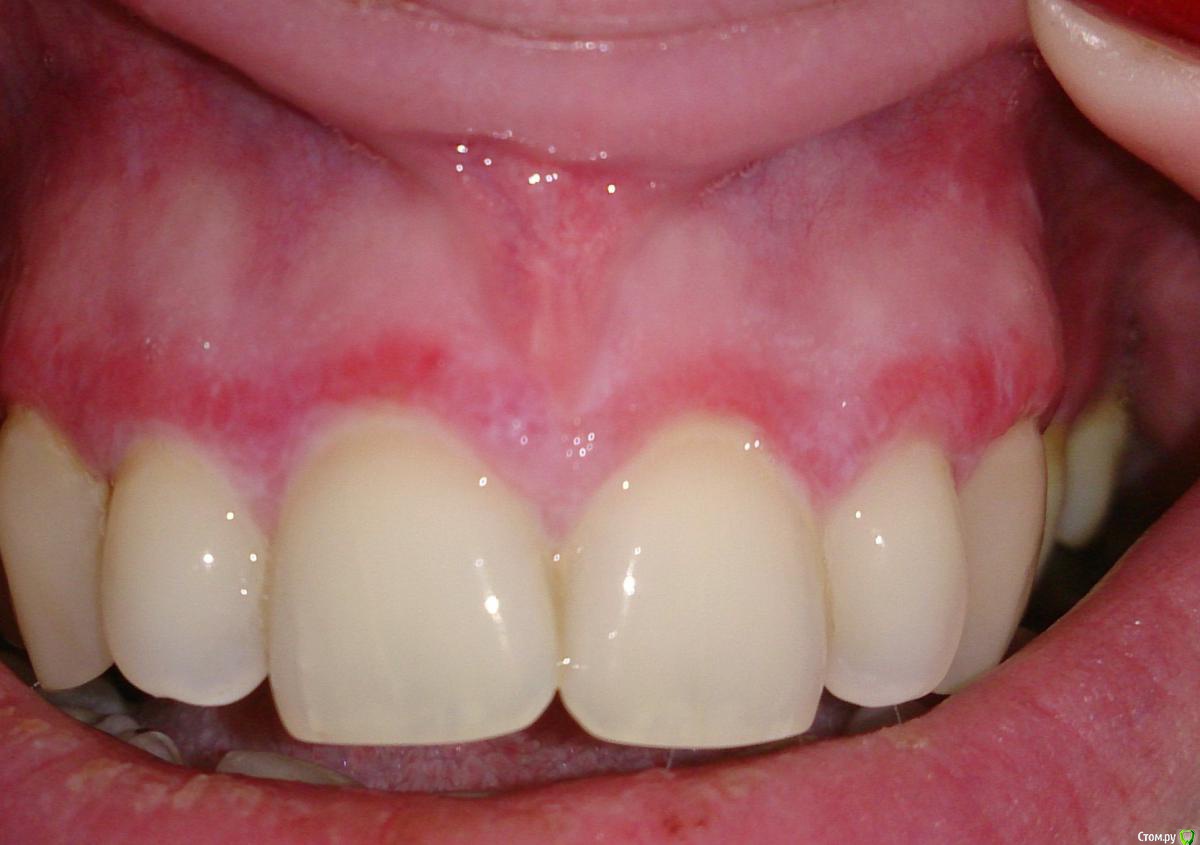

Милanora Опубликовано 4 января, 2017 Поделиться Опубликовано 4 января, 2017 Добрый день! Помогите пожалуйста, не знаю что уже и думать. Проходила лечение у стоматолога и парадонтолога, врачи в один голос говорят, что у меня классический КПЛ и если меня он не беспокоит, то лечить его и не нужно. Десны иногда побаливают, но язвочек нет. Решила еще для очистки совести сходить к дерматологу. Сделала мазки на грибок, отрицательно. Врач дерматолог сказала, что лечением слизистой стоматологи занимаются, но согласилась посмотреть. КПЛ отменила, сказала, что если он есть на слизистой рта, то и на теле обязательно должен быть. У меня нет никаких высыпаний на теле. Поставила лейкоплакию, на мой вопрос, от чего она вообще бывает (я курю и у меня неправильный прикус, отчего иногда прикусываю щеку) она послала сдавать анализ на ВИЧ, а курение и прикус не могут быть причиной, по ее словам. Я вообще в шоке.Посмотрите пожалуйста фото, может быть Вы что-то подскажите мне.... Ссылка на комментарий

Л Ю С Я Опубликовано 4 января, 2017 Поделиться Опубликовано 4 января, 2017 По фото у Вас одна из разновидностей КПЛ. Может быть изолировано поражение слизистой. Для окончательного диагноза нужен очный осмотр стоматолога. Курение обязательно нужно исключить Ссылка на комментарий

Salma Опубликовано 5 января, 2017 Поделиться Опубликовано 5 января, 2017 тоже склоняюсь к кпл Ссылка на комментарий

ПалСаныч Опубликовано 5 января, 2017 Поделиться Опубликовано 5 января, 2017 Имхо кпл Ссылка на комментарий